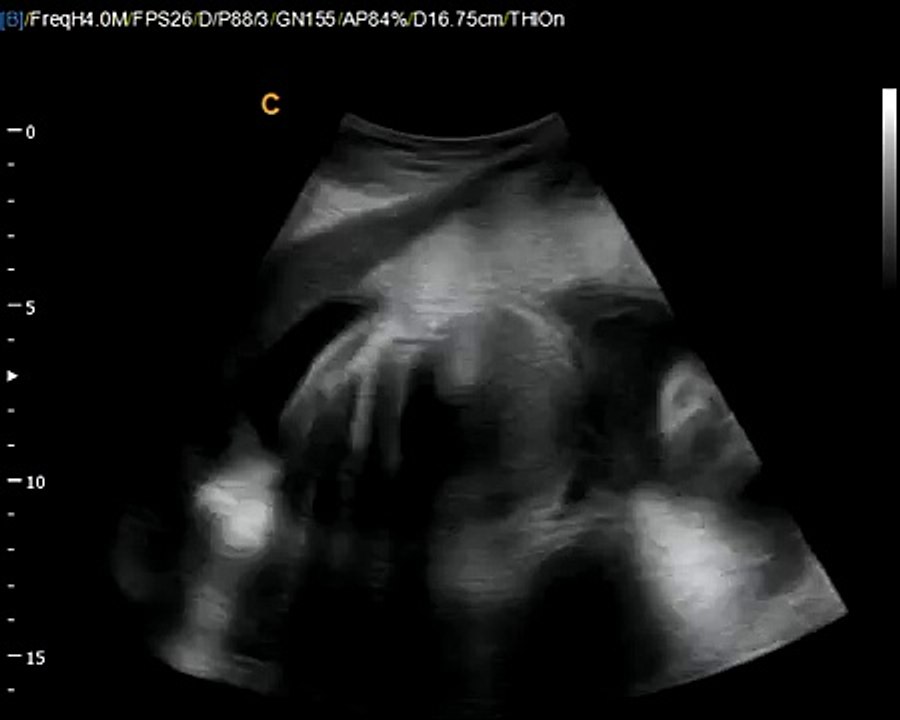

:: RO ::<br /><br />Extrase din DVD-ul 'Martor ocular - Generaţia următoare' de dr. Shari Richards.<br /><br />"O imagine valorează cât o mie de cuvinte"... mai ales dacă imaginea este realizată cu ajutorul unei tehnologii de ultimă oră! Urmarea unui alt documentar celebru - "Fereastra spre interior" ("Window to the Womb") – "Martor ocular" prezintă o călătorie fascinantă de-a<br />lungul celor 38 de săptămâni de sarcină, călătorie facilitată de tehnologia ultrasunetelor, a ecografiei 3D si 4D. Perfect pentru seminarii în scoli, pentru săli de asteptare în spitale si pentru centre de consiliere.<br /><br />Aceasta variantă are 15' şi este descriptivă (cu subtitluri).<br /><br />15' excerpt from Dr. Shari Richard's DVD 'Eyewitness - The next generation' - a fascinating journey through the womb with the newest digital ultrasound technology.<br /><br />"A picture is worth a thousand words," especially if it is from the next generation of 3D and 4D ultrasound imaging. Many of you have experienced the powerful educational and life saving effects of Shari Richard's original "Window to the Womb." Now she will take you on a fascinating new journey using the newest digital ultraound technology.<br /><br />This short version shows fetal development described using subtitles.